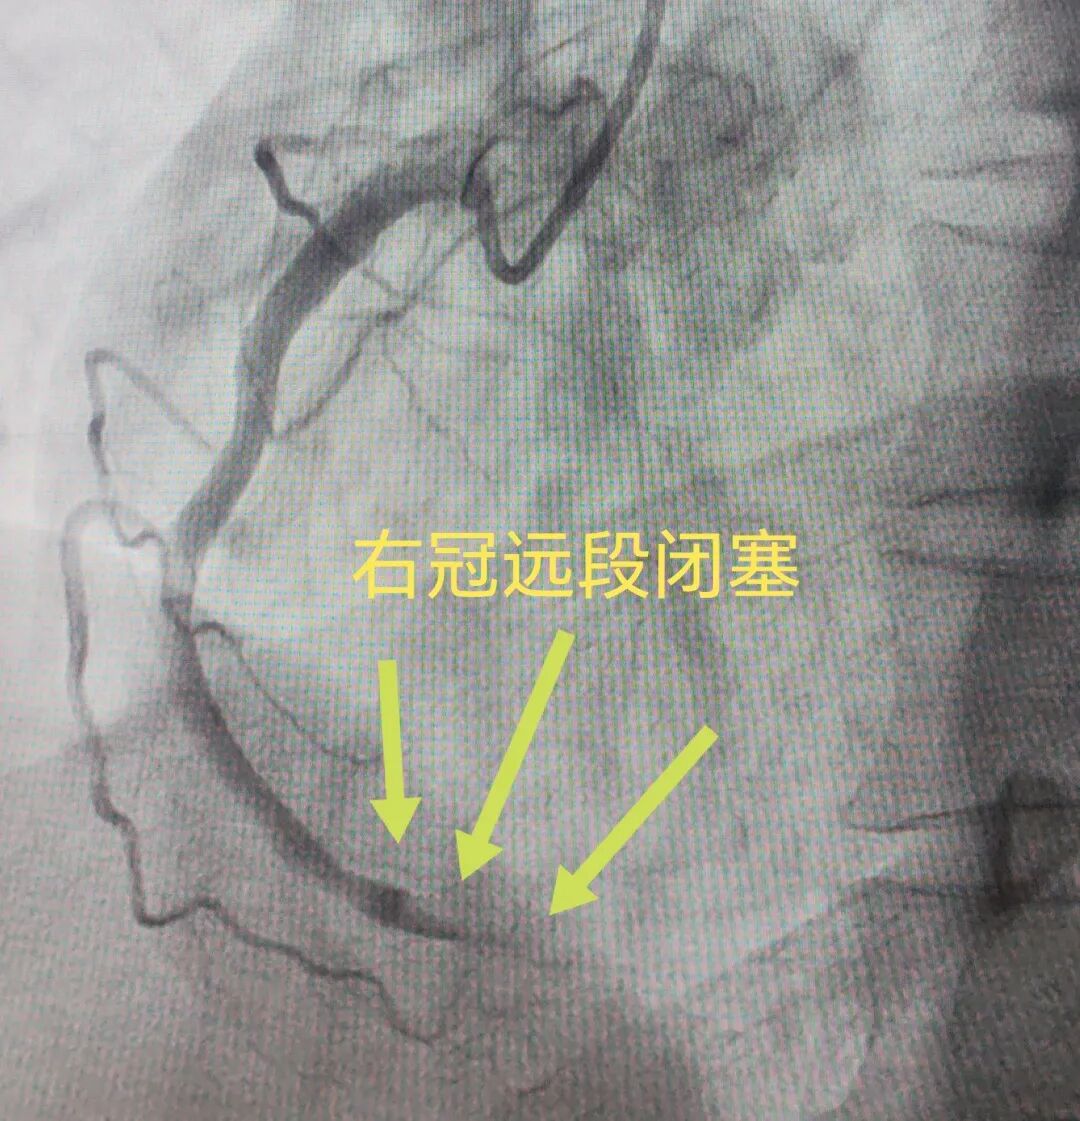

医院立即启动胸痛中心诊疗流程,迅速完成 POCT 快速检测心脏标志物,心血管内科急会诊后决定行急诊冠脉造影检查。术中发现患者右冠状动脉中远段充满血栓,完全闭塞,病情极其凶险。